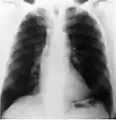

Radiografía

En este segmento de las imágenes médicas se puede encontrar desde los más simples exámenes de Rayos X hasta estudios complejos como el sistema digestivo. Las imágenes son obtenidas gracias a las diferentes capacidades que poseen los tejido de atenuar las radiaciones x, han sido utilizados en el ámbito médico desde su descubrimiento en 1895 por Wilhelm Conrad Röntgen y hasta nuestros días son ampliamente utilizados para realizar diagnósticos diferenciales en el área de la traumatología (pesquisa de fracturas, alteraciones de los huesos y malformaciones), a la vez permiten visualizar algunos órganos de menor densidad como los pulmones, en cuyo caso es posible detectar diferentes patologías que afectan a este órgano cono es el caso de la acumulación de polvos que al ser inhalados causan enfermedades definidas como silicosis. Todo estudio radiográfico está compuesto, a lo menos, por dos proyecciones lo que permite visualizar la estructura estudiada en dos planos perpendiculares.

Las imágenes digitales que se adquieren hoy en día, ya sea en radiología digital indirecta (CR) o directa (DR), presentan una gran ventaja debido a la potencialidad que su manejo informático ofrece, en el cual es posible sobre la base de una imagen adquirida aplicar diferentes herramientas como filtros que permiten mejorar el realce de los borde, suavizar, analizar el histograma y realizar análisis de la calidad de la imagen obtenida. Estas herramientas están disponibles en las consolas de procesado de imágenes de los equipos radiológicos, pero también existen programas dedicados como ImageJ que permiten realizar el análisis de las imágenes, ya sean de uso médico o no. Una de la funcionalidades de ImageJ es la posibilidad de "retocar" la imagen aplicando filtros como los que se observan en las siguientes imágenes en las cuales hemos aplicado a la imagen base de una radiografía de cráneo (al centro) un filtro que permite suavizar la imagen (Imagen 1) y luego a la misma imagen le hemos aplicado un filtro de reforzamiento de los bordes (Imagen 2).

Imagen 1

Imagen 2

Imagen basal